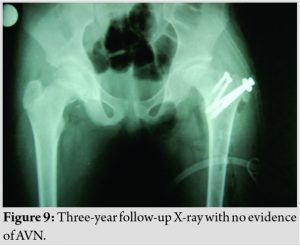

The patient is now able to do active straight leg raises against resistance (Fig. 7), walks independently pain-free with good range of movements, including hip flexion of more than 90* (Fig. 8) after 3-year follow-up with no radiological signs of avascular necrosis of femoral head (Fig. 9).